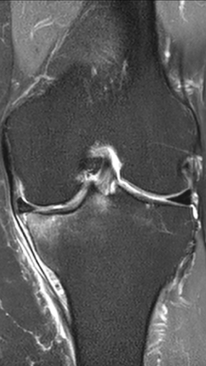

Асептический некроз коленного сустава

4 процедуры ФДТ, 9 процедур MBST, 15 процедур ИПМТ

Параметры изменяются в зависимости от процедуры

Дата публикации: 22.08.2025 14:27:03